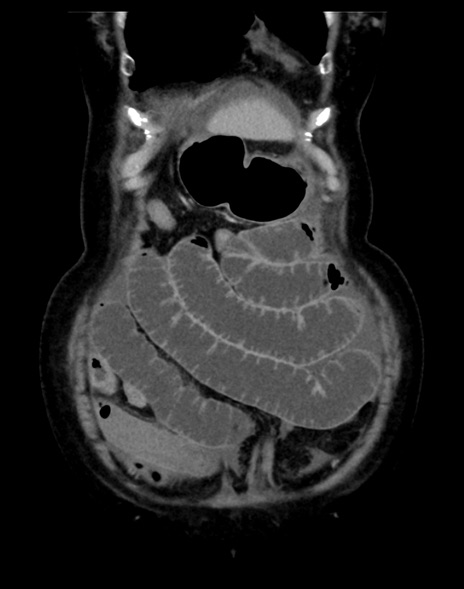

(横断像)1日半後